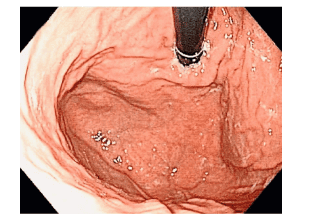

Image 2: Normal appearance of the gastroesophageal fold: the cardia tightly embraces the scope

During digestive endoscopy, when examining various parts of the stomach in an upright position, the endoscopist will maneuver the scope to investigate the regions of the fundus and cardia, observing the mucosal folds converging at the junction of the esophagus and stomach, which is the gastroesophageal fold.